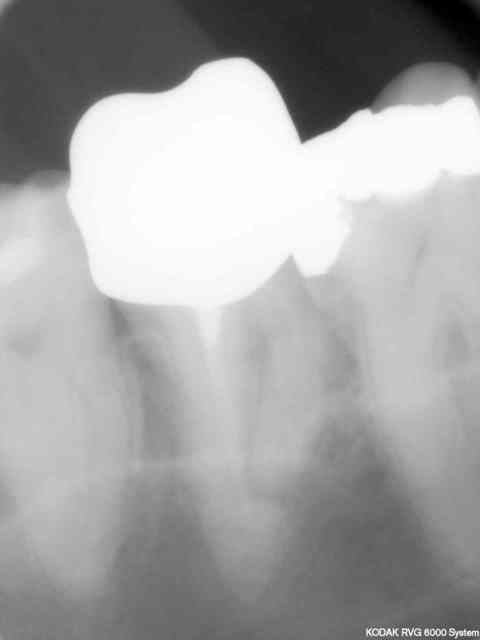

J'en étais resté au thermocompactage: simple, rapide et pas cher et utilisable avec de la gutta "low cost" genre R&S.

L'idéal en dentisterie sécu.

L'irrigation alternée avec Salvizol et hypochlorite permet en plus d'avoir très souvent des puffs comme les pros ...

Inconvénient: il faut impérativement faire un cône d'arrêt à LT-1 et avoir un bon tug back à cette longueur sinon c'est le dépassement assuré.

Il y a parfois des casses de pointes de Mc Spadden comme sur la radio de la 14 mais comme c'est un instrument stérile noyé dans de la gutta ça ne (me) pose pas de problème.